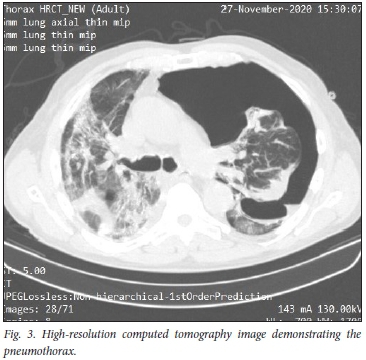

A man in his seventies was admitted in November 2020 with COVID-19 pneumonia and treated with low-molecular-weight heparin (LMWH), antibiotics and supplements. He was discharged 5 days later, but within 72 hours was readmitted with a high fever and severe dyspnoea. At that stage, clinically he had severe pneumonia confirmed on a repeat high-resolution CT scan of the chest. Heparin was restarted and dexamethasone 6 mg daily added. The response was slow but satisfactory, and he was discharged 9 days later feeling quite well.

A few days later, while watching television at home, he had a sudden bout of coughing and slight haemoptysis, followed by severe dyspnoea. He only reported to casualty the following morning, and was found to be in severe respiratory distress with a sats of 80% on room air. Clinically a large left-sided tension pneumothorax was present (confirmed on CT scan of the chest, Fig. 3). An intercostal drain was inserted with dramatic symptomatic improvement. The further course was uncomplicated.

Pneumothorax and tension pneumothorax are uncommon but well-described complications of COVID-19 pneumonia. In a study of 3 368 patients with suspected COVID-19 pneumonia, 902 patients were nasopharyngeal swab-positive, and there were 6 cases (0.66%) of spontaneous pneumothorax.[6] Four of these cases were associated with mechanical ventilation and 2 occurred spontaneously.

Pneumothorax usually presents with increasing dyspnoea and may be confused with worsening pneumonia or thromboembolism. This is an important complication of COVID-19 to recognise, as it is easily remedied by insertion of an intercostal drain as in the case described.